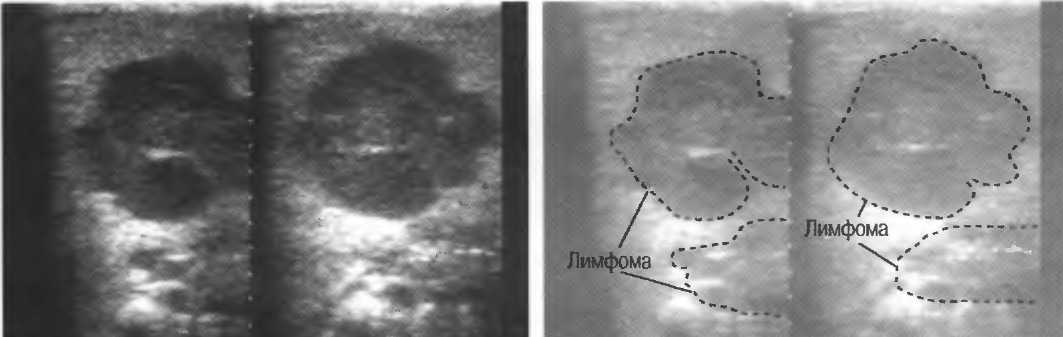

УЗИ лимфоузлов при лимфоме Ходжкина

Раздел: Образы вокруг